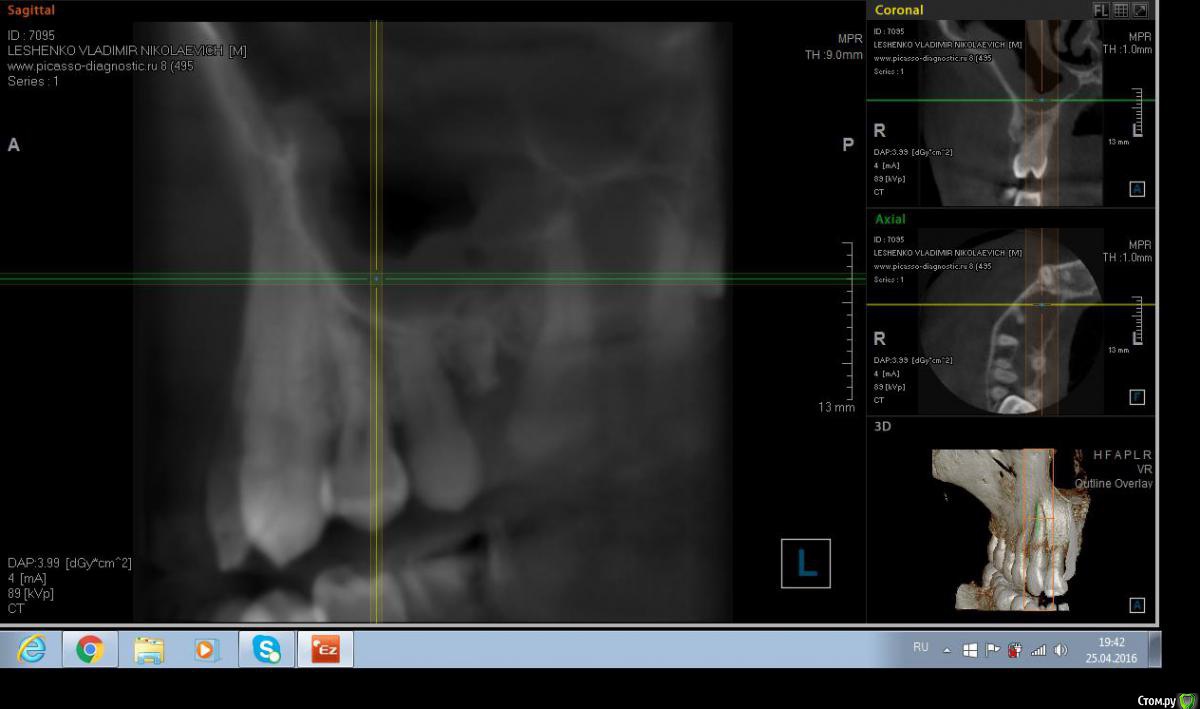

Salma Опубликовано 26 апреля, 2016 Поделиться Опубликовано 26 апреля, 2016 Обратился пациент с болью в области десны в районе 15 и 16 зубов, при осмотре немного отечная десна в области этих зубов, на небе ( не знаю как сказать по другому) между этими же зубами есть щель, с небольшим количеством отделяемого. В общем то промыла , положила метрогил, отправила на кт. Похоже на корень , думаю удалять, но вопросы такие: 1. достаточно ли просто удалить или нужно будет костью присыпать? и что там насчет гайморовой? Ссылка на комментарий

red_butler Опубликовано 26 апреля, 2016 Поделиться Опубликовано 26 апреля, 2016 Да похоже на корень от первого моляра. Просто удалить. Ссылка на комментарий

wladdX Опубликовано 26 апреля, 2016 Поделиться Опубликовано 26 апреля, 2016 Похоже нёбный корень от шестого. Удаляйте. 1 1 Ссылка на комментарий

Salma Опубликовано 26 апреля, 2016 Автор Поделиться Опубликовано 26 апреля, 2016 спасибо ответившим, я думаю что скорее молочный, так как шестерка у пациента есть Ссылка на комментарий

red_butler Опубликовано 26 апреля, 2016 Поделиться Опубликовано 26 апреля, 2016 спасибо ответившим, я думаю что скорее молочный, так как шестерка у пациента естьа восьмой есть? Судя по наклону и расстоянию до премоляра, похоже что все таки от шестерки. Ссылка на комментарий